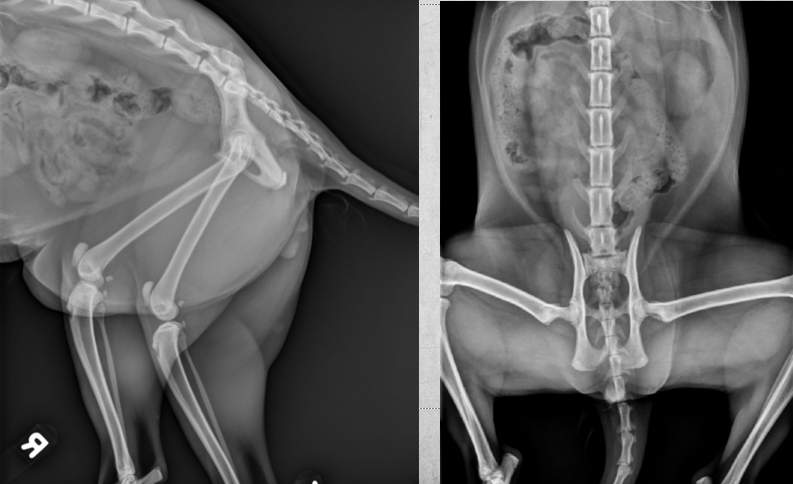

2 years old male castrated cat

Severe sudden onset lameness of pelvic limb

Displaced capital physeal fracture of the left femoral head with mild cranial displacement of the femoral neck. On the frog-legged VD projections, this displacement is not visualizing so well.

Most of the physes of the pelvic limbs are at least partially open, including the intact right femoral capital physis (castrated young).

Diagnosis: Left sided capital physeal fracture of the left pelvic limb and delayed physeal closure in both hind limbs.